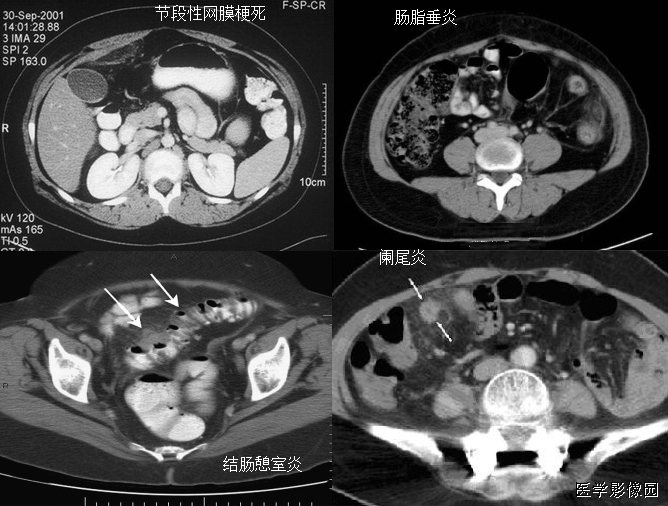

3、不成比例脂肪绞缠征

不成比例脂肪绞缠主要指的是增厚肠壁和周围脂肪在数量方面比例的严重失衡。在少数急性胃肠道疾病中,以肠壁相邻的肠系膜为中心而不是以肠壁为中心,因此肠壁周围脂肪增厚明显高于肠壁厚度。和这一征像相关的疾病主要包括4类:憩室炎、肠脂垂炎、网膜梗死和阑尾炎。胃肠道的大多数炎性疾病包括感染性的、非感染性的和局部缺血性的病变,都是以肠道为中心。这些疾病的肠壁增厚程度往往超过相邻脂肪条索的厚度。但是对于少数以肠壁临近系膜为中心的疾病,脂肪增生明显超过肠壁的厚度。

左上图:右侧腹横肌深面、胆囊内前方梭形囊性病变,有壁但不均匀,略有强化。与腹横肌成锐角,腹横肌肥厚。周围脂肪模糊,有索条点状影。

右上图:邻近降结肠远端系膜壁旁可见一卵圆形类似脂肪密度的病变,周边可见火焰样炎性改变,邻近肠壁有轻微增厚,无明显脓肿及肠梗阻征象。

左下图:肠壁增厚,结肠袋襞显影不良,以及结肠周围脂肪束条状改变。

右下图:CT显示壁明显增强的管状结构(箭头),右中腹的脂肪系膜反应。